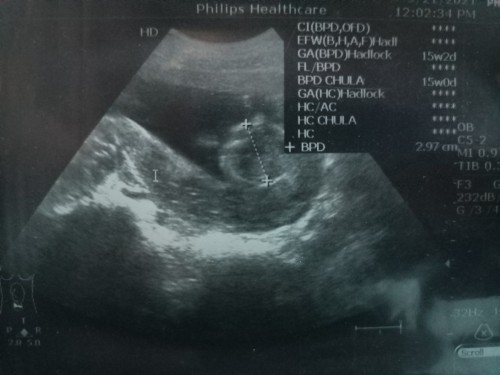

ไปซาวด์ดูวันนี้ ในเครื่องบอก15วีค+2วัน แต่ถ้านับตามปจด. ก็คือ14วีค+5วัน สรุปเราต้องเชื่ออันไหนมากกว่ากันคะ